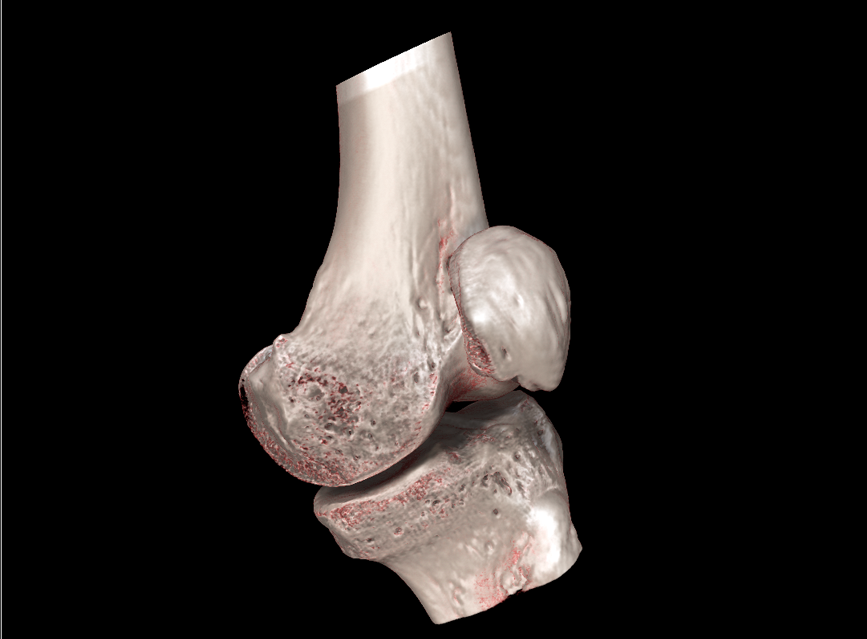

HRCT

High Resolution Computed Tomography. Outstanding image quality with a voxel size up to 100 µm